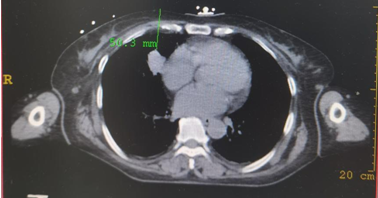

近日,肿瘤内科开展IQQA-Guide智能手术导航机器人引导下的肿瘤穿刺定位、活检术,成功为一名小肠间质瘤伴右肺结节患者完成肺部结节穿刺活检。根据病理结果,诊断为双原发肿瘤(小肠间质瘤、肺腺癌)。

病例简介:一例小肠间质瘤伴右肺结节患者

拟行:IQQA-Guide导航下右肺穿刺活检术

▲上图:IQQA-Guide术中全程三维量化实时定位、跟踪、引导及监控,辅助医生精准穿刺

▲上图:穿刺到位